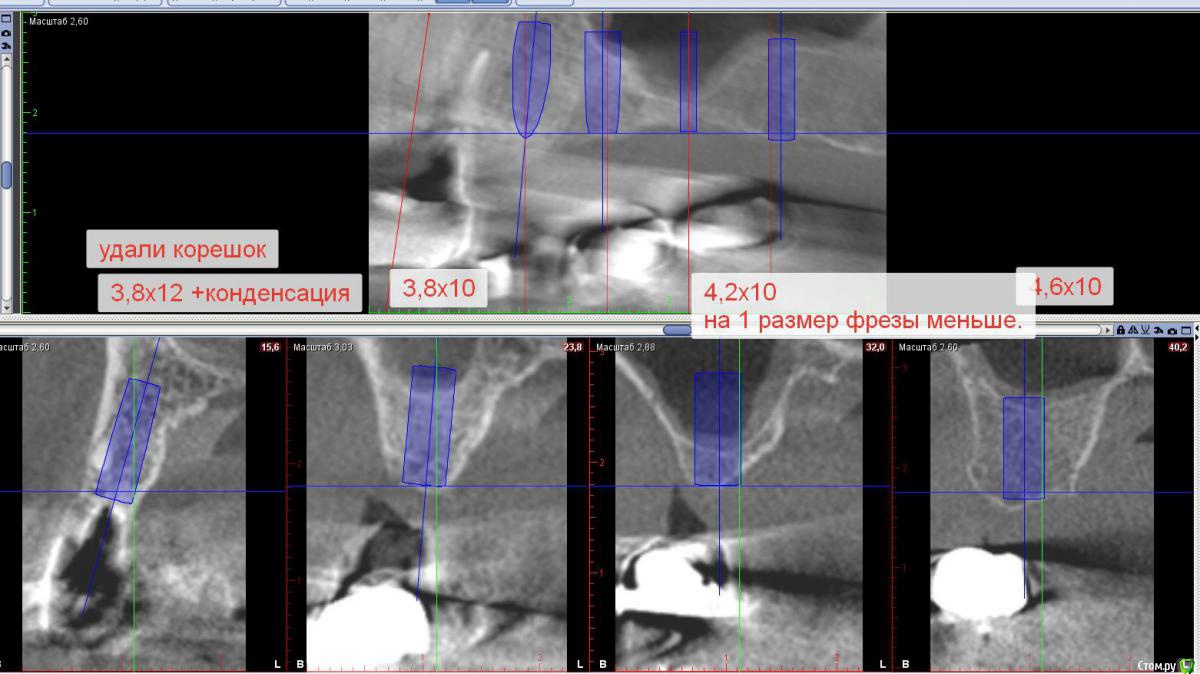

Sergiosse Опубликовано 10 июня, 2017 Поделиться Опубликовано 10 июня, 2017 (изменено) Первый раз делал с приглашенным коллегой, в этот раз сам.Графт церабон 1гр смешал с плазмой и нарезаным сгустком А ПРФ. Хотел делать микст, набрав джейлом ауто с бугра, не получилось, кость как пенопласт. Окно закрыл мембраной АПРФ. Дистальный имплант вкрутил с торком 10 Н\см. Скажу ортопеду чтобы соединил в блок 6 и 7 коронки.Хотелось бы комментариев от опытных коллег все ли сделал правильно? Изменено 10 июня, 2017 пользователем Sergiosse Ссылка на комментарий

Sergiosse Опубликовано 12 июня, 2017 Автор Поделиться Опубликовано 12 июня, 2017 Коллеги,вы бы не ставили 26 , и сделали мостовидный протез с опорой на 14 15 И 17 имплантанты? Какой долгосрочный прогноз выживаемости такой конструкции? Я отказался от этого варианта,так как Кость в обл. 27 мягкая как пенопласт,торк 10Н/см. Считаю ,что рискованно использовать его как опору в мостовидном протезе,и планирую его шинировать с 26, чтобы минимизировать риск перегрузки. К. Миш рекомендуют для Кости 4 класса перед постоянным протезированием ,в течение 4 месяцев давать прогрессивную нагрузку на временных коронках. Ссылка на комментарий